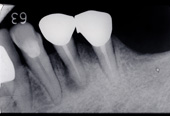

■症例写真

歯周病により溶けてしまった骨を再生造成し補正します。